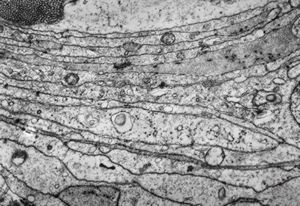

F,50y. | progressive multifocal leukoencephalopathy- viral particles in a glial cell

F,50y. | progressive multifocal leukoencephalopathy- viral particles in a glial cell

F,50y. | progressive multifocal leukoencephalopathy- viral particles in a glial cell